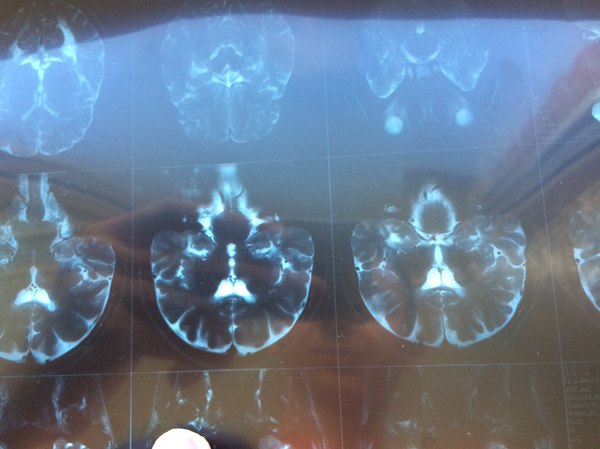

Тут было не всё так просто. Да, МРТ было у меня на руках (вот пара снимков оттуда. Несимметричные светлые пятна - очаги или бляшки). Немного очагов - был момент ремиссии.